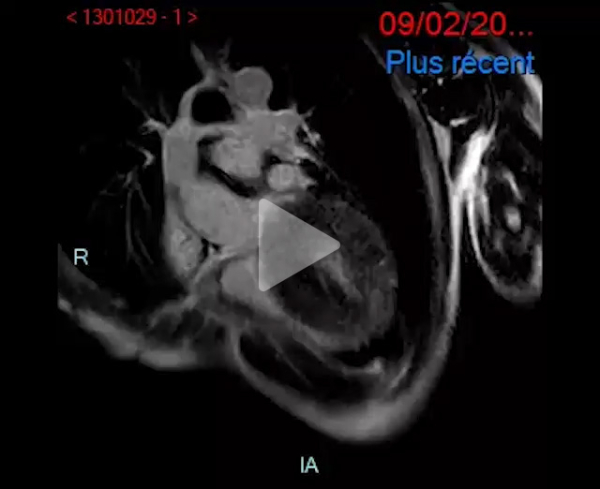

IRM cardiaque en février 2023 :

- Cardiomyopathie hypertrophique évoluée

- Dysfonction biventriculaire sévère, FEVG 19%, FEVD 22%

- VG dilaté

- IRM en faveur d'une pathologie de surcharge : pas d'argument pour un Fabry en IRM

- Faisceau d'arguments plutôt évocateur d'une amylose cardiaque

Vidéo 2